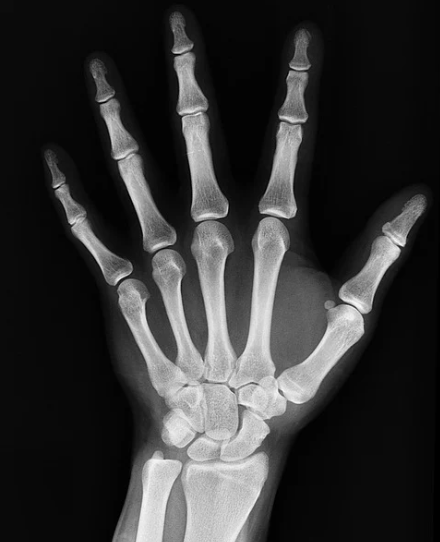

뼈에 금이 갔을때 증상 - 멍이나 붓기

뼈에 금이갔을때 나타나는 증상 두번째는 멍이나 부음이 있을 수있습니다. 외부와의 충돌로 인해 자주 발생하는 멍은 뼈에 금이 갔을 경우에도 나타날 수있습니다. 다친 부위가 너무 심하게 붓거나 멍이 들어있는 경우 뼈와 가깝게 있는 근육이나 혈관이 다치게 되어 멍이나 부음증상이 생길 수있습니다.

뼈에 금이 갔을때 증상 - 변형

뼈에 금이갔는데도 모르고 지나치거나 대수롭지 않게 넘기는 경우 뼈에 변형이 생길 수도있습니다. 타박상과 비슷한 증상이라 병원에 내원하지 않고 뼈에 금이간것을 그냥 방치한다면 증상을 더 악화시킬 수도있지만 뼈가 어긋나게 붙어 버리거나 사지의 길이가 단축되어 지는 경우 등등 좋지 않은 방향으로 붙기때문에 증상이 계속된다면 꼭 병원에 내원하시는 것이 좋습니다.

뼈에 금이 갔을때 증상 - 점상출혈

모세혈관 파열등의 원인으로 인해 피부나 점막등에서 검붉은 반점을 나타내는 미세한 출혈을 나타내는 점상출혈은 가벼운 외상에 의해 출혈이라면 처음엔 선명한 자주색을 나타내다가 시간이 지날수록 점차 갈색으로 옃어지면서 며칠 뒤 없어지곤 합니다. 또한 골절 부위에 있는 체액이 증가함에 따라 출혈이 발생하게되어 부종과 종창까지 나타날 수있다고 합니다.